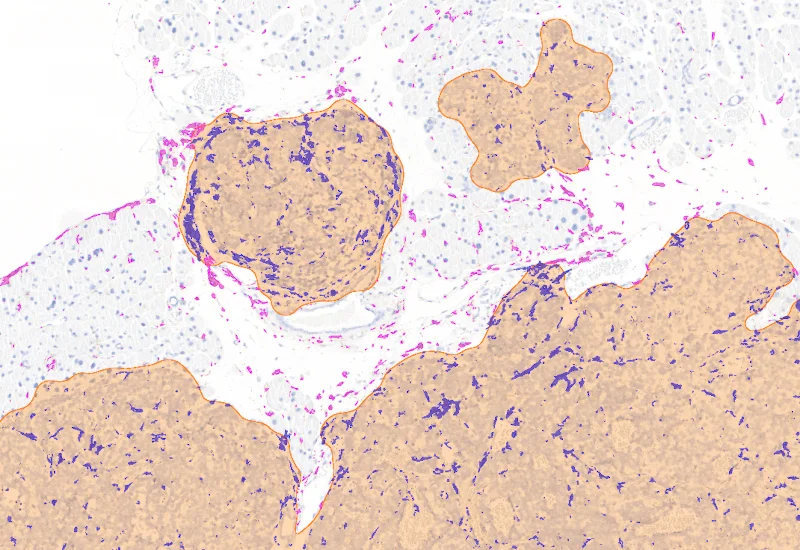

Proximity map tumor